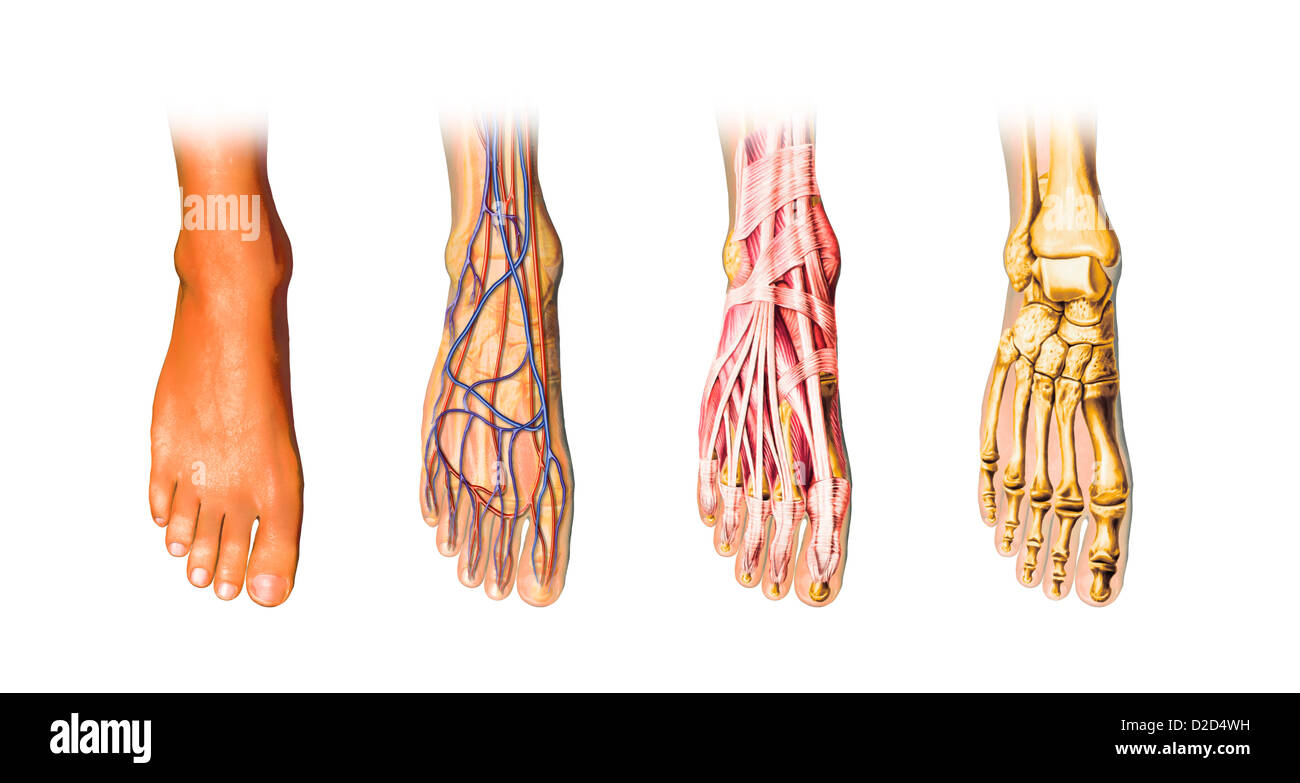

RF2ABM669–La médecine et les soins de l'illustre le tableau, les droits de l'anatomie du pied : Peau et tissus ectodermaux, os, muscles nerfs, vaisseaux sanguins